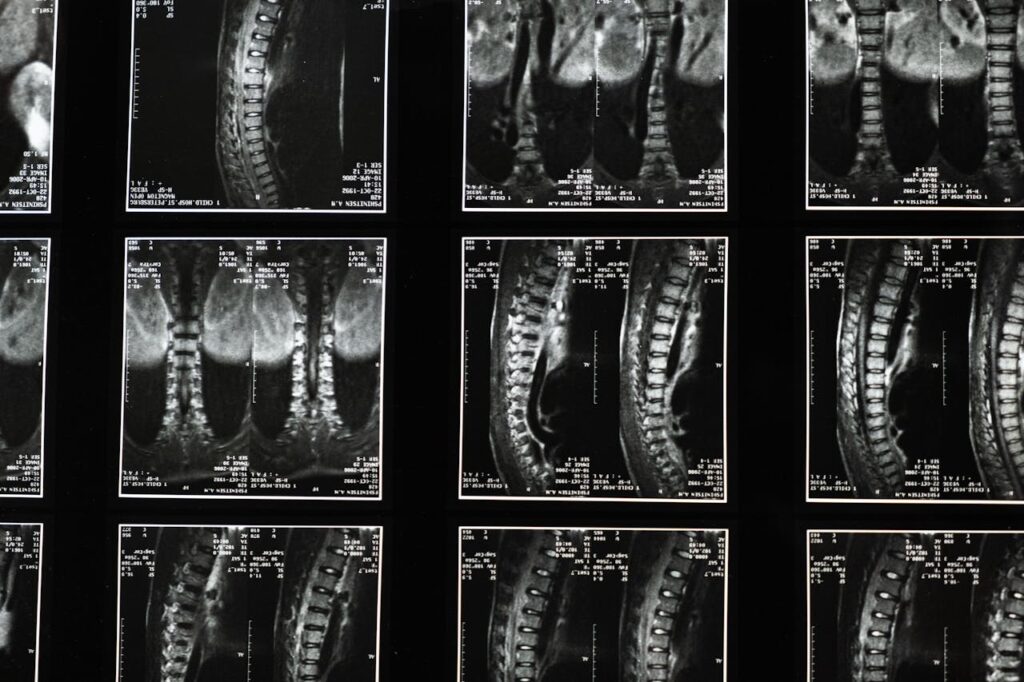

Kręgosłup to skomplikowana struktura i może ulec różnym uszkodzeniom – od lekkich do bardzo ciężkich. W systemie odszkodowań rodzaj oraz nasilenie urazu mają duże znaczenie przy ustalaniu kwoty. Trzeba dokładnie zbadać i udokumentować każdy objaw, bo nawet pozornie niewielkie urazy mogą dawać skutki przez długi czas.

Do urazów należą m.in.: złamania kręgów, uszkodzenia rdzenia, urazy odcinka szyjnego, naciągnięcia mięśni, przemieszczenia i wypadnięcia dysków. Każdy przypadek ocenia się osobno, biorąc pod uwagę wpływ na życie poszkodowanego.

• Dokumenty medyczne: diagnozy, wyniki (RTG, MRI, TK), zalecenia, recepty – z informacją, że uraz jest skutkiem wypadku.